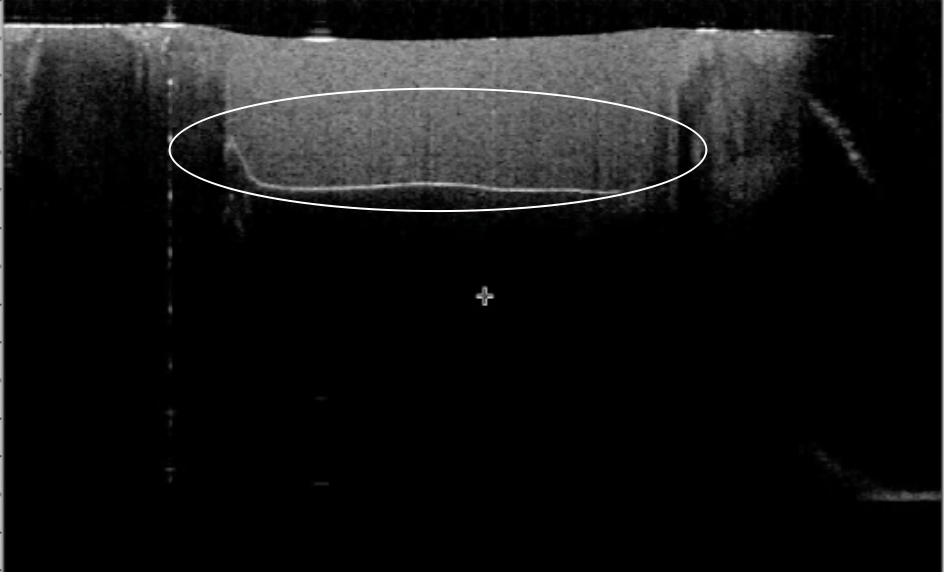

These images from a video in the study Hayashi J, et al. Real-Time Imaging of Gap Progress during and after Composite Polymerization. J Dent Res. 2017; 1-7 show adhesive failure. The first image shows composite placed in a restoration. The second shows the composite after it has been cured, the white line at the bottom showing a gap between the adhesive material and the tooth, which can cause the restoration to fall out or create sensitivity.

We use specific techniques that create a bond to your tooth without this gap, so the bond lasts longer and eliminates sensitivity.